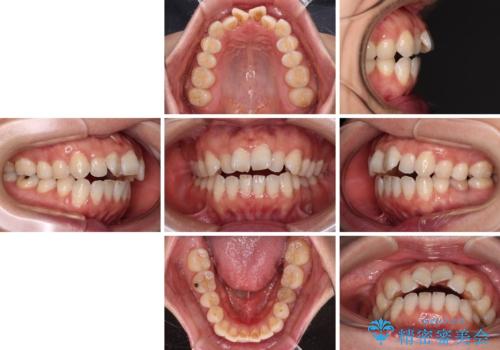

【モニター】飛び出した上顎前歯 補助装置を併用したインビザライン矯正治療

- 上下前歯が非接触となり、前方に突出していることを気にして来院された患者様です。

上下の前後差が大きいため、インビザライン単独での上顎歯列移動は困難と判断し、補助装置により上顎歯列を後方移動させ、その後インビザラインにて仕上げていくこととしました。

また、舌の突出癖が非接触の原因の大きな要因と考えられるため、舌のトレーニングをしっかり行っていくよう指導しました。